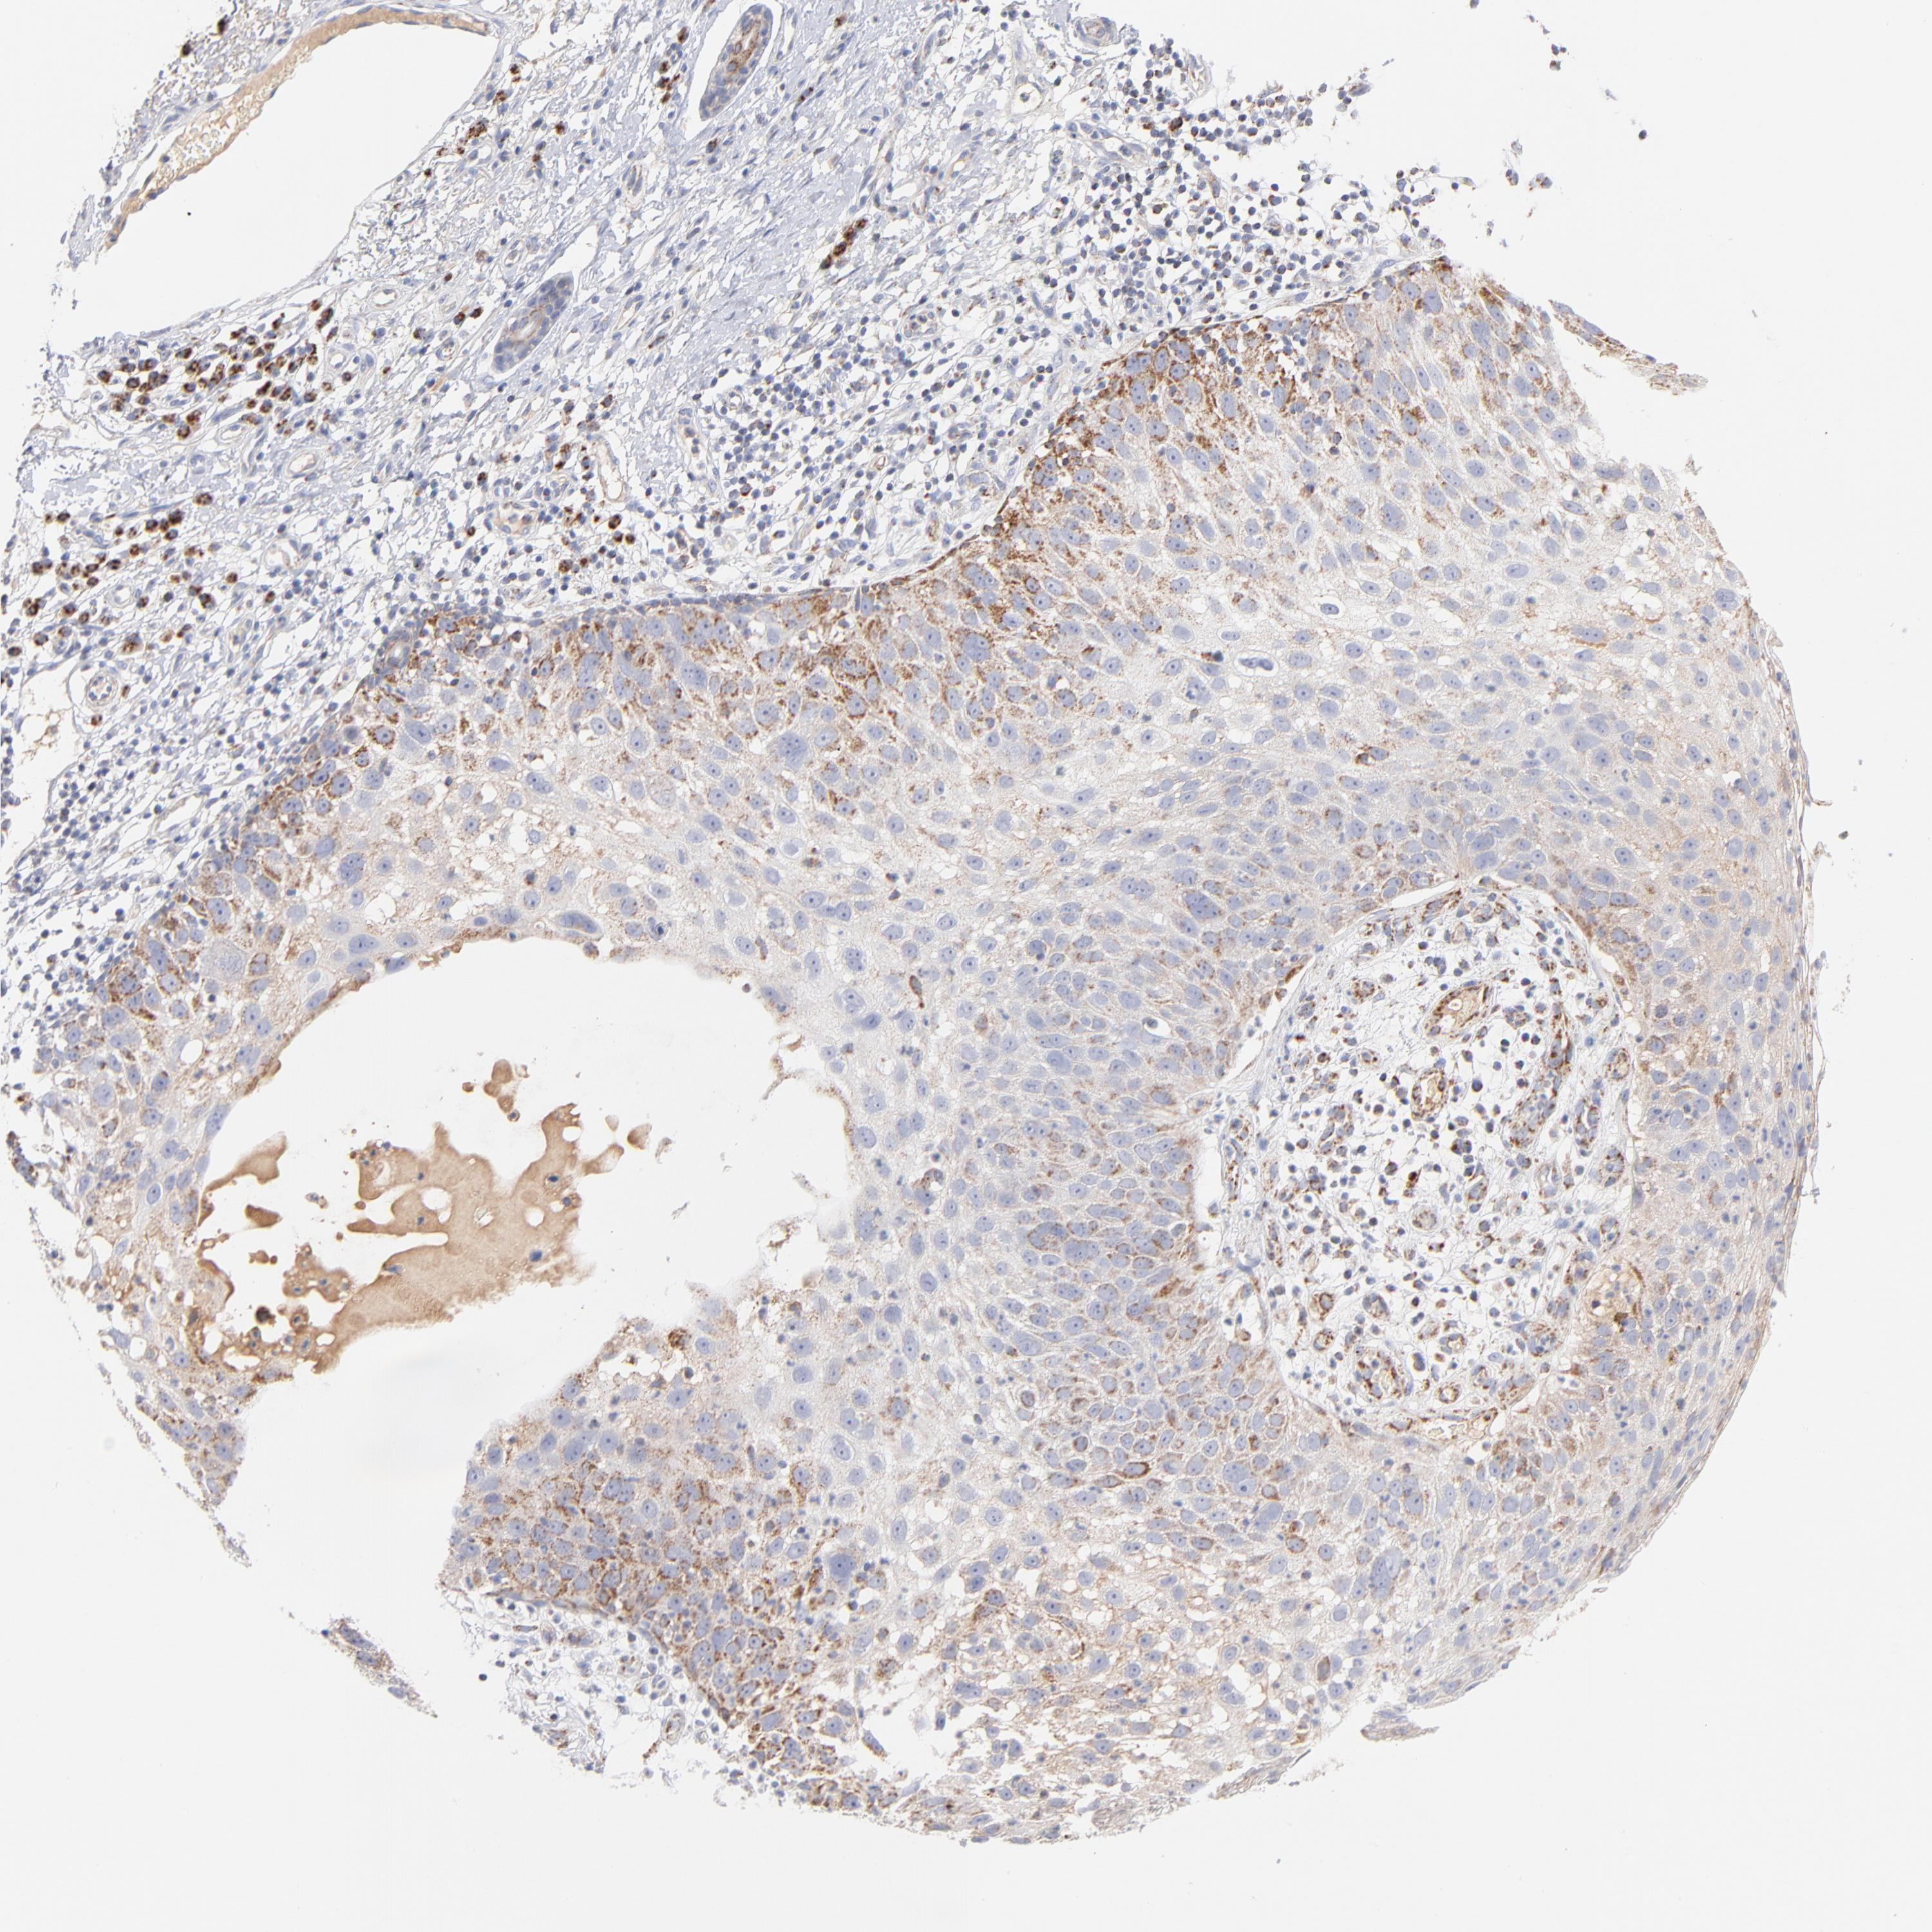

Basal cell and squamous cell cancer

SKIN CANCER - Protein expressioni

A mouse-over function shows sample information and annotation data. Click on an image to view it in a full screen mode. Samples can be filtered based on level of antibody staining by selecting one or several of the following categories: high, medium, low and not detected. The assay and annotation is described here.

Antibody stainingi

Antibody staining in the annotated cell types in the current human tissue is reported as not detected, low, medium, or high, based on conventional immunohistochemistry profiling in selected tissues. This score is based on the combination of the staining intensity and fraction of stained cells.

Each image is clickable and will lead to virtual microscopy that enables deeper exploration of all samples and also displays staining intensity scores, fraction scores and subcellular localization as well as patient and tissue information for each sample.

Antibody HPA040786

Antibody CAB003782

Staining

High

Medium

Low

Not detected

Intensity

Strong

Moderate

Weak

Negative

Quantity

>75%

75%-25%

<25%

None

Location

Nuclear

Cytoplasmic/membranous

Cytoplasmic/membranous,nuclear

Squamous cell carcinoma, NOS

Squamous cell carcinoma, metastatic, NOS